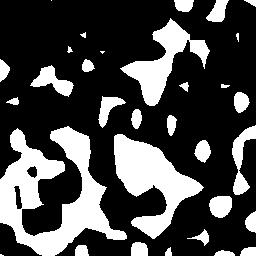

To better retain the deep features of an image and solve the sparsity problem of the end-to-end segmentation model, we propose a new deep convolutional network model for medical image pixel segmentation, called MC-Net. The core of this network model consists of four parts, namely, an encoder network, a multiple max-pooling integration module, a cross multiscale deconvolution decoder network and a pixel-level classification layer. In the network structure of the encoder, we use multiscale convolution instead of the traditional single-channel convolution. The multiple max-pooling integration module first integrates the output features of each submodule of the encoder network and reduces the number of parameters by convolution using a kernel size of 1. At the same time, each max-pooling layer (the pooling size of each layer is different) is spliced after each convolution to achieve the translation invariance of the feature maps of each submodule. We use the output feature maps from the multiple max-pooling integration module as the input of the decoder network; the multiscale convolution of each submodule in the decoder network is cross-fused with the feature maps generated by the corresponding multiscale convolution in the encoder network. Using the above feature map processing methods solves the sparsity problem after the max-pooling layer-generating matrix and enhances the robustness of the classification. We compare our proposed model with the well-known Fully Convolutional Networks for Semantic Segmentation (FCNs), DecovNet, PSPNet, U-net, SgeNet and other state-of-the-art segmentation networks such as HyperDenseNet, MS-Dual, Espnetv2, Denseaspp using one binary Kaggle 2018 data science bowl dataset and two multiclass dataset and obtain encouraging experimental results.